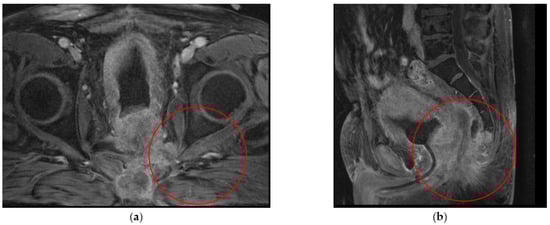

| 3 | Ovarian cancer T3cNxM1 IVa st.1 | Combined cytoreductive (initially optimal) operation: posterior supralevator evisceration of the small pelvis. Resection of the right dome of the diaphragm. Resection of the greater and lesser omentum. Obstructive resection of the sigmoid colon. Total peritonectomy. Cholecystectomy, splenectomy, appendectomy. Resection of the right ureter (Figure 8). | 390 |